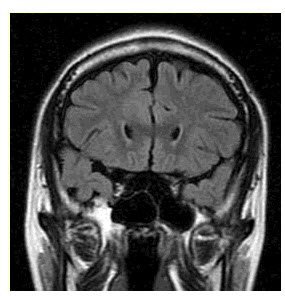

患者男,37岁,因“发作性意识障碍伴双眼发直26年”来诊。无明显先兆,每次发作持续1min左右。既往有发热惊厥史;智力体格发育正常。

该MRI表现为(提示患者行颅脑MRI检查,结果见下图。)()

A.无特异性异常

B.左侧海马硬化

C.右侧海马硬化

D.双侧海马硬化

E.左侧额叶发育异常

F.右侧额叶发育异常